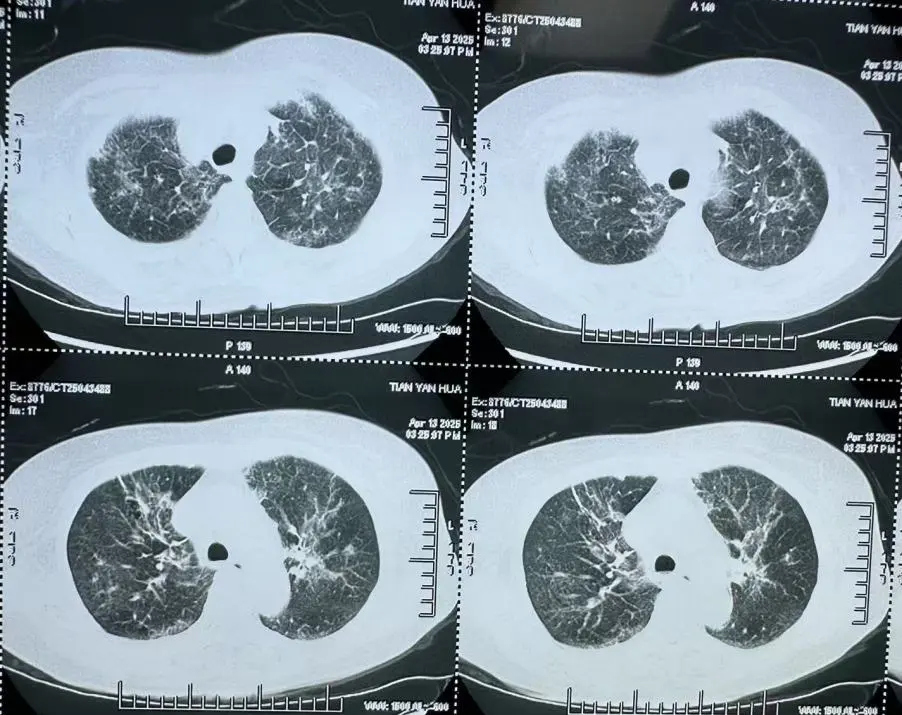

非HIV-PCP肺部影像

非HIV-PCP的早期癥狀與普通肺炎相似,但進展更快,48小時內(nèi)可能引發(fā)呼吸衰竭。有免疫缺陷病史(如腫瘤化療、器官移植、風濕免疫病長期用藥)等高危人群一旦出現(xiàn)持續(xù)發(fā)熱>1周,抗生素治療無效;干咳、進行性呼吸困難;血氧飽和度<93%等癥狀應(yīng)立即到呼吸與危重癥醫(yī)學(xué)科就醫(yī),進行支氣管鏡肺泡灌洗檢查。